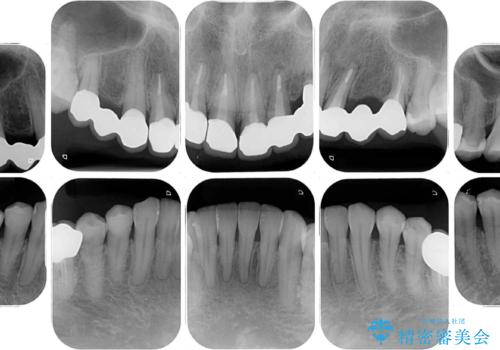

- 他院で矯正治療を終えたものの、むし歯や欠損部の治療が進められないとのことで来院された患者様です。

欠損部や、銀歯やむし歯の大きな歯はセラミッククラウンやブリッジに、小さいむし歯はセラミックインレーにて治療を行うこととしました。

歯肉の状態がとても、短期間でスムーズに治療を終えることができました。